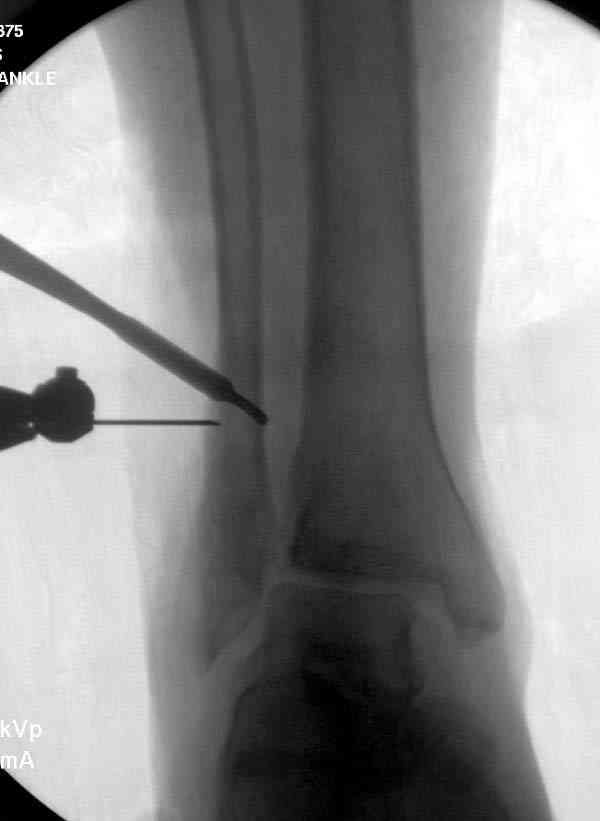

Здесь представлено решение похожей проблемы. Больной в течение года

лечился консервативными мерами, и боли в голеностопе были основным

показанием к операции.

Проведена обычная стандартная процедура по исправлению

неудовлетворительного состояния голеностопного сустава, где кроме

удлинения малоберцовой с применением compression tension device за

проксимальный конец пластины, проведено замещение трикортикальным

графтом из крыла, освобождение синдесмоза и медиальной щели от

фибротических масс с фиксацией.